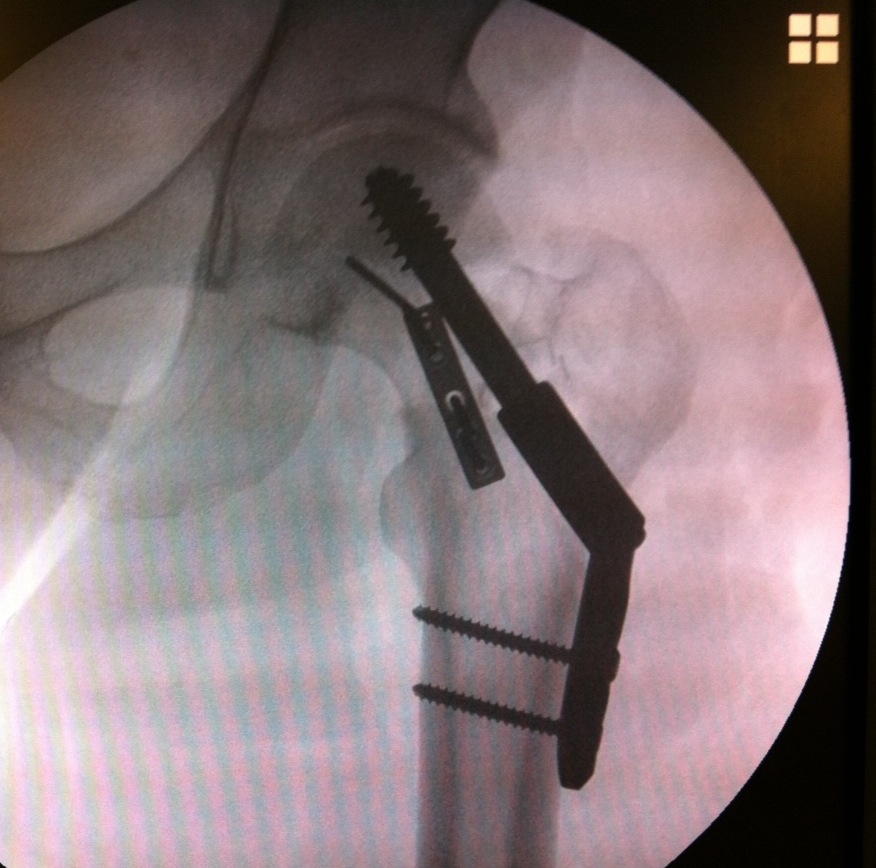

Fixation

DHS /Cannulated screws / FNS

Unstable fracture - augment with a medial buttress plate on inferior neck

Medial buttress plate